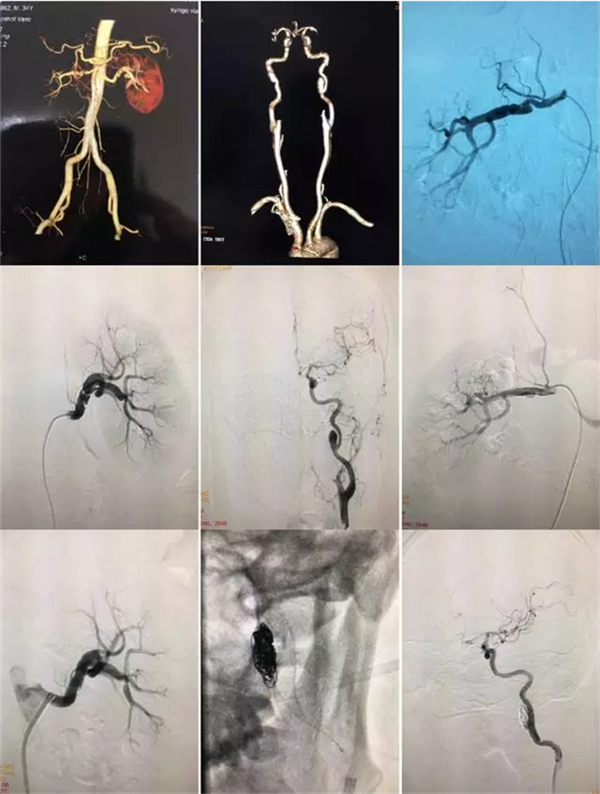

就在联合体共建推进会前一周,河池市中医医院推荐了一名“肾动脉狭窄”病人,经与一附院介入科罗耀昌主任沟通,联系病人收住我院外五科。病人是35岁男性,头昏脑胀,血压高达190一210/90一110mmHg!经全面检查诊断为:动脉肌纤维发育不良(病情累及了双侧肾动脉、双侧颈内动脉并多发严重狭窄、夹层瘤形成),经介入科团队共同努力,通过两次微创介入治疗行球囊支架成形术和支架辅助十微弹簧圈栓塞后,三支严重狭窄伴夹层瘤血管完全恢复通畅,血压恢复正常,精神状态焕然一新!

手术前后影像